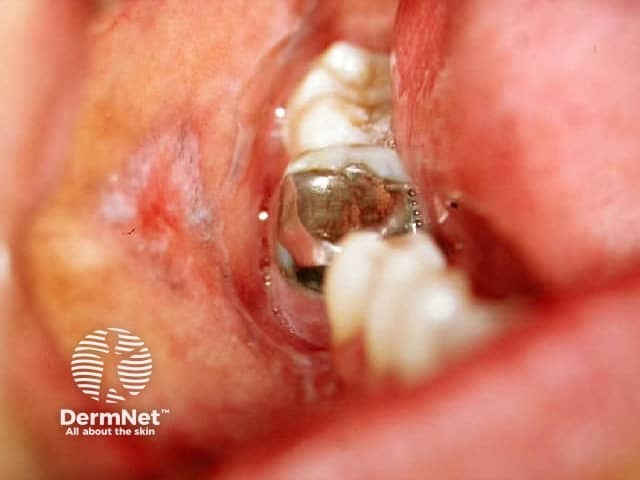

Lichenoid reaction to amalgam

Atrophic/erosive lichen planus

Erosive pattern